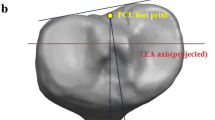

Each anatomical landmark was defined on the 3D models of the femur and tibia. The prominent point of lateral femoral epicondyle and the medial femoral epicondylar sulcus were marked on femoral 3D models to establish the SEA (Fig. 1A). The line perpendicular to the projection of the SEA on the tibial osteotomy surface was drawn (Fig. 2). In the tibial 3D models, five anatomical landmarks were described including three anterior anatomical landmarks (the medial boundary, the medial sixth point, and the medial third point of the patellar tendon attachment site) and two posterior anatomical landmarks (the geometric center of the tibial osteotomy plane and the middle of the PCL termination) (Fig. 1). The middle point of the line passing through the innermost and outermost positions of the resected tibial plateau was considered as the geometric center of the tibial osteotomy surface. Six tibial rotational axes were established (Fig. 3):

Bony landmarks for rotational alignment reference axes. A the surgical transepicondylar axis (a) the medial epicondylar sulcus; (b) the prominent point of lateral epicondyle. B (c) the medial border point of the patellar tendon at the attachment site. (d) the medial one-sixth point of the patellar tendon at the attachment site. (e) the medial third point of the patellar tendon at the attachment site. C (O) the midpoint of posterior cruciate ligament insertion. D (f) the innermost position of the tibial plateau at the resection level. (g) the outermost positions of the tibial plateau at the resection level. (GC) the geometric center of the tibial osteotomy surface